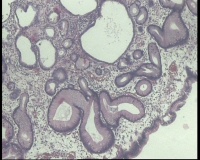

镜下见十二指肠粘液腺明显增多,排列密集,中心有少量平滑肌组织间隔,局灶腺体扩张,是十二指肠息肉还是报十二指肠腺腺瘤?

图4